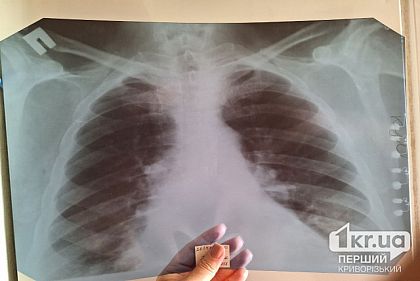

Верховная Рада приняла Закон о преодолении туберкулеза в Украине

Лечение туберкулеза в Украине станет более доступным для пациентов, а система диагностики – будет соответствовать мировым стандартам. Верховная Рада приняла Закон о преодолении туберкулеза.Об этом...